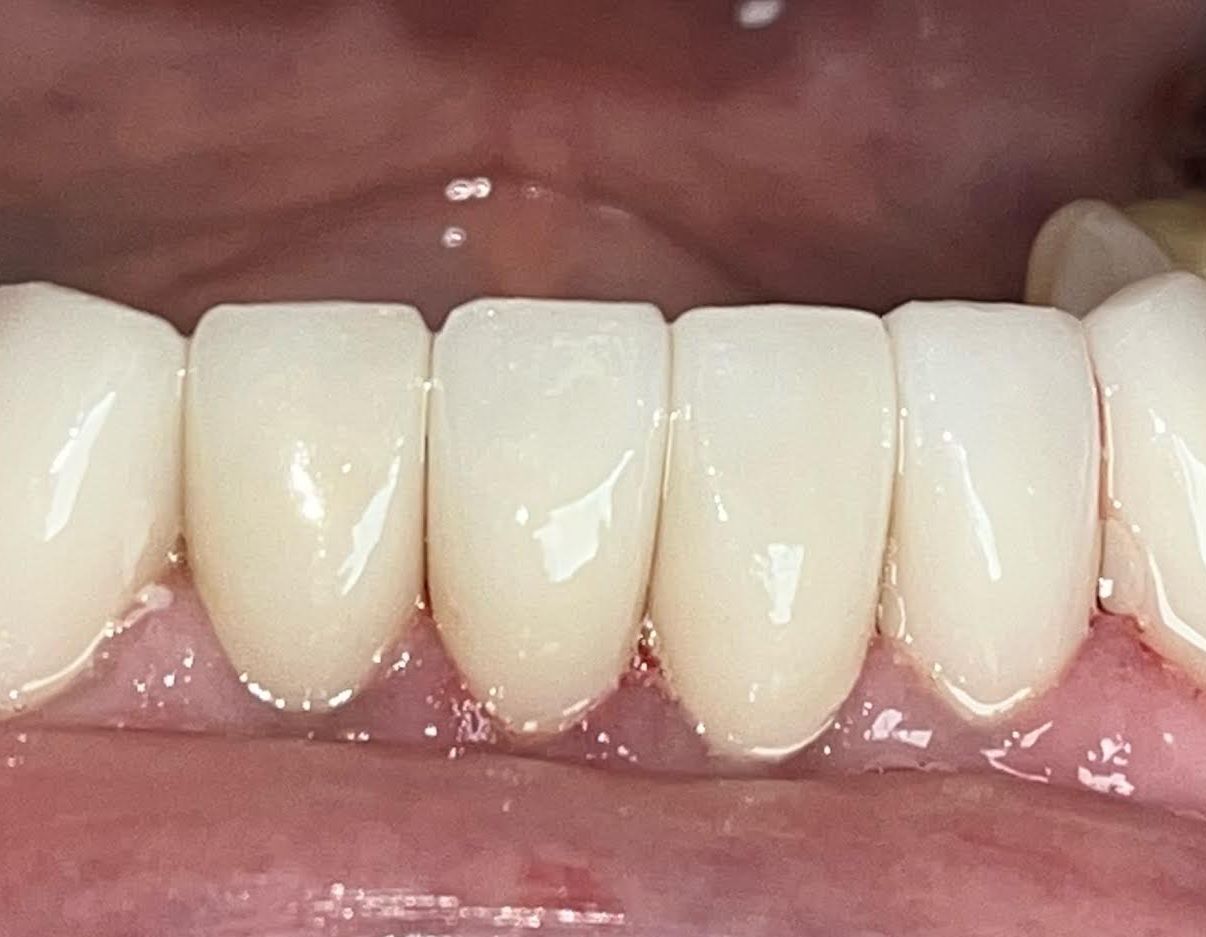

Dental Crowns Treatment

This patient was in need of crowns. We were able to rejuvenate their smile with a set of crowns